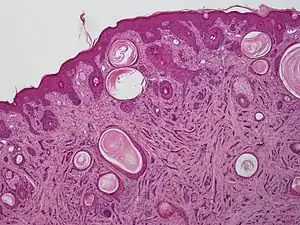

| A microscopic view of microcystic adnexal carcinoma | |